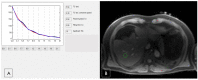

Recently, medical radiology has undergone significant improvements in patient management due to advancements in image acquisition by the last generation of machines, data processing, and the integration of artificial intelligence. In this way, cardiovascular imaging is one of the fastest-growing radiological subspecialties. In this study, a compressive review was focused on addressing how and why CT and MR have gained a I class indication in most cardiovascular diseases, and the potential impact of tissue and functional characterization by CT photon counting, quantitative MR mapping, and 4-D flow. Regarding rectal imaging, advances in cancer imaging using diffusion-weighted MRI sequences for identifying residual disease after neoadjuvant chemoradiotherapy and [18F] FDG PET/MRI were provided for high-resolution anatomical and functional data in oncological patients. The results present a large overview of the approach to the imaging of diffuse and focal liver diseases by US elastography, contrast-enhanced US, quantitative MRI, and CT for patient risk stratification. Italy is currently riding the wave of these improvements. The development of large networks will be crucial to create high-quality databases for patient-centered precision medicine using artificial intelligence. Dedicated radiologists with specific training and a close relationship with the referring clinicians will be essential human factors.